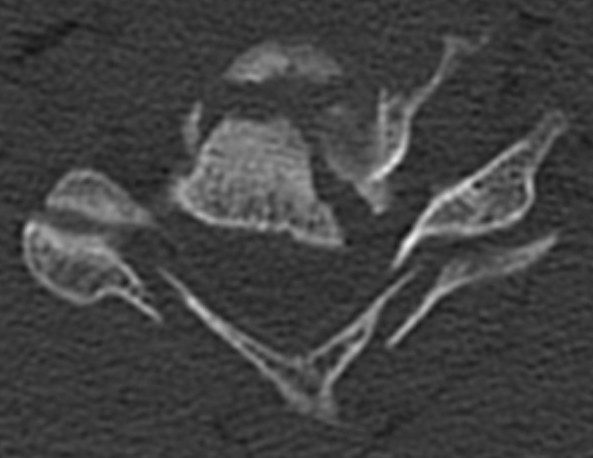

Canal compromise / neurological injury

- retropulsed fragments

- typically one or two main retropulsed fragments

CT